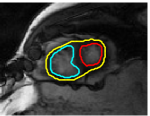

The problem above is a generalization of Horn & Schunck optical flow. Note that solving for the Horn & Schunck optical flow within each region separately does not lead to motions such that at the interface, they have equal normal components (see Figure 1), whereas the solution of (5) to be presented in subsequent sections does. Note that computing Horn & Schunck optical flow in each region requires boundary conditions (and typically they are chosen to be Neumann boundary conditions: and on ). Note that replacing these boundary conditions with the boundary constraint (6) does not specify a unique solution. Also, while Horn & Schunck optical flow computed on the whole domain naturally gives a globally smooth motion, which by default satisfies matching normals at the interface, this is not natural for the ventricles / myocardium, where different motions exist in the regions (see Figure 2), and the motions should not be smoothed across the regions.

![]() |

| image + boundary | next image | within region optical flow | our method |